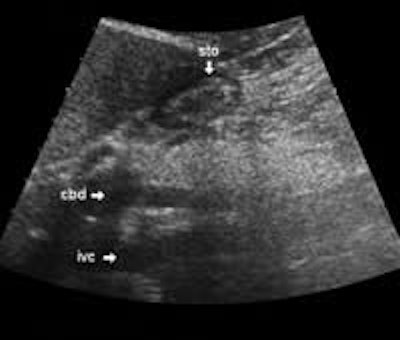

The following study describes anatomical landmarks in the ordinary pancreas of a thin patient:

Transverse planes in caudal direction:

The main bile duct runs from the liver hilum to the right of and above the portal vein into the right dorsal part of the pancreatic head, where it runs vertically into the duodenum. The pancreatic duct typically runs along the body and tail to join the common bile duct near the duodenum. The gastroduodenal artery is sometimes seen in its position along the front margin of the pancreatic head, where it runs in a nearly parallel direction to the common bile duct. Like the common bile duct and pancreatic duct, however, the gastroduodenal artery is not always clearly seen due to its small diameter. The duodenum covers the right and bottom margins of the pancreatic head.

More or less fat tissue can be seen separating the pancreas from the following structures: The head and body of the pancreas are located below the liver, and below and generally behind the distal part of the stomach. The pancreatic head and body are located in front of the inferior vena cava and the aorta with the celiac trunk. To the far left, the tail of the pancreas has a position below the spleen and above the left kidney.